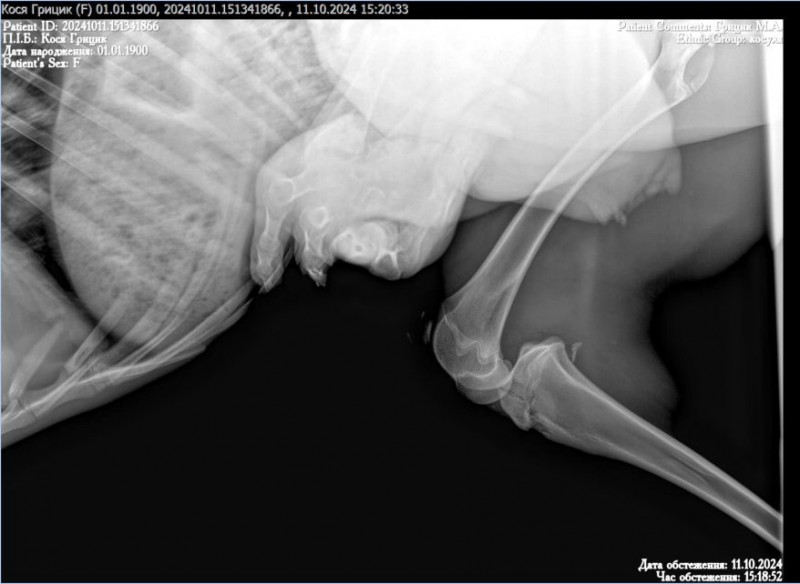

Як йдеться у дописі, травмувалась тварина приблизно десять днів тому та вже перенесла операцію по ампутації задньої кінцівки. Крім цього, має ще численні серйозні травми.

До дівчини косуля потрапила вже після операції і, як виявилось, після ампутації на нозі залишили гострий фрагмент кістки, через що тканини постійно травмуються. Як наслідок, є набряк.

Крім цього, на іншій нозі у косулі розірвані зв’язки, тому тварина не може піднятися на ноги. Це значно ускладнює процес її лікування та реабілітації.